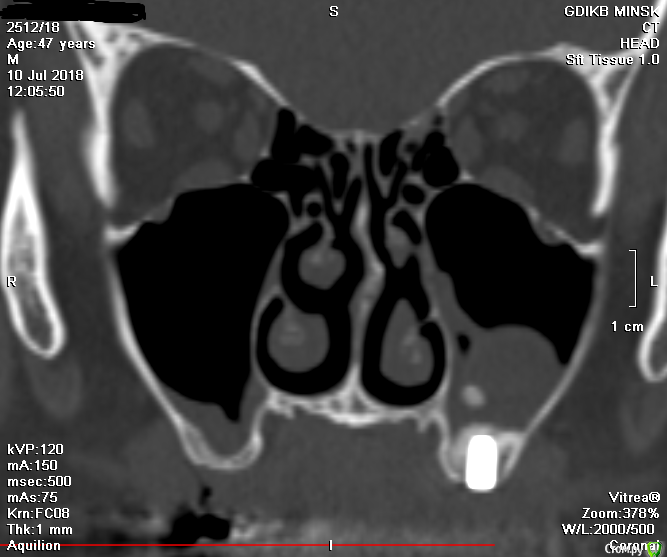

V20 Опубликовано 28 апреля, 2019 Поделиться Опубликовано 28 апреля, 2019 (изменено) Доброго времени суток , помогите пожалуйста разобраться с ситуацией.В мае 2018 года был проведен синус лифтинг с одновременной установкой 3 имплантов, Спустя 5-7 дней на фоне приема антибиотиков(Аугментин), развился левосторонний гайморит. Прошел курс консервативного лечения, пазуха успокоилась.Было решено протезироваться . В феврале 2019 года при откручивании ФД выкрутился имплант (по центру ) и образовался свищ, . Была сделана пластика свища. Сообщение закрылось.На настоящий момент сохраняется чуть заметная припухлость щеки в проекции пазухи и немного поднывает десна.(больше в районе крайнего импланта) На ощупь языком в месте соприкосновения десны и щеки небольшая припухлость ( похоже по проекции разреза).Что интересно с утра десна не болит начинается дискомфорт чуть позже. Уважаемые доктора , помогите пожалуйста в дальнейшей тактике - мнения врачей кардинально расходятся(снимки через неделю после синус лифтинга Снимок 3 месяца назад после консервативного лечения у ЛОРа Последний снимок (2 месяца назад) И еще хотелось бы услышать Ваше мнение о импланте на месте 24 зуба Заранее спасибо. Изменено 28 апреля, 2019 пользователем V20 Ссылка на комментарий

Bier Опубликовано 1 мая, 2019 Поделиться Опубликовано 1 мая, 2019 Я бы раскрыл как при синуслифтинге, чтобы оценить что там такое. По КТ все не очень хорошо. Ссылка на комментарий

Bier Опубликовано 1 мая, 2019 Поделиться Опубликовано 1 мая, 2019 синусит и есть не хорошо. У него есть причина. 1 Ссылка на комментарий

V20 Опубликовано 16 мая, 2019 Автор Поделиться Опубликовано 16 мая, 2019 синусит и есть не хорошо. У него есть причина.Здравствуйте! Пойду настаивать на ревизии,хотел бы услышать еще Ваше мнение по поводу импланта рядом с клыком (не в пазухе ли он) и еще если удалять дальний имплант, (там где был синус лифтинг) что делать если образуется сообщение между пазухой, опять лоскутным методом или по свежему достаточно просто ушить лункку? Ссылка на комментарий